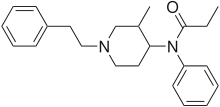

Anilidopiperidines

- 3-Allylfentanyl

- 3-Methylfentanyl

- 3-Methylthiofentanyl

- 4-Phenylfentanyl

- Alfentanil

- α-Methylacetylfentanyl

- α-Methylfentanyl

- α-Methylthiofentanyl

- Benzylfentanyl

- β-hydroxyfentanyl

- β-hydroxythiofentanyl

- β-Methylfentanyl

- Brifentanil

- Butyrfentanyl

- Carfentanil

- Fentanyl

- Lofentanil

- N-Methylcarfentanil

- Mirfentanil

- Ocfentanil

- Ohmefentanyl

- Parafluorofentanyl

- Phenaridine

- R-30490

- Remifentanil

- Sufentanil

- Thenylfentanyl

- Thiofentanyl

- Trefentanil

Structures